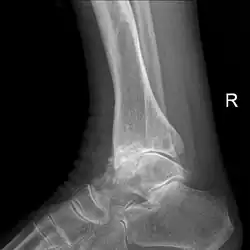

Lateral X-ray scan of ankle with secondary osteoarthritis

Lateral

Frontal X-ray scan of ankle with secondary osteoarthritis

Frontal

Secondary osteoarthritis of the ankle (due to an old bone fracture) in an 82-year-old woman